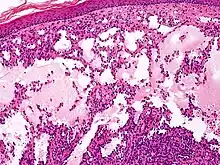

Cavernous lymphangioma, H&E stain. Irregular, dilated spaces are visible in dermis.

Lymphangiomas have traditionally been classified into three subtypes: capillary and cavernous lymphangiomas and cystic hygroma. This classification is based on their microscopic characteristics. A fourth subtype, the hemangiolymphangioma is also recognized.[9]

Cavernous lymphangiomas

Composed of dilated lymphatic channels, cavernous lymphangiomas characteristically invade surrounding tissues.

Microscopically, the vesicles in lymphangioma circumscriptum are greatly dilated lymph channels that cause the papillary dermis to expand. They may be associated with acanthosis and hyperkeratosis. There are many channels in the upper dermis which often extend to the subcutis (the deeper layer of the dermis, containing mostly fat and connective tissue). The deeper vessels have large calibers with thick walls which contain smooth muscle. The lumen is filled with lymphatic fluid, but often contains red blood cells, lymphocytes, macrophages, and neutrophils. The channels are lined with flat endothelial cells. The interstitium has many lymphoid cells and shows evidence of fibroplasia (the formation of fibrous tissue). Nodules (A small mass of tissue or aggregation of cells) in cavernous lymphangioma are large, irregular channels in the reticular dermis and subcutaneous tissue that are lined by a single layer of endothelial cells. Also an incomplete layer of smooth muscle also lines the walls of these channels. The stroma consists of loose connective tissue with a lot of inflammatory cells. These tumors usually penetrate muscle. Cystic hygroma is indistinguishable from cavernous lymphangiomas on histology.[4]